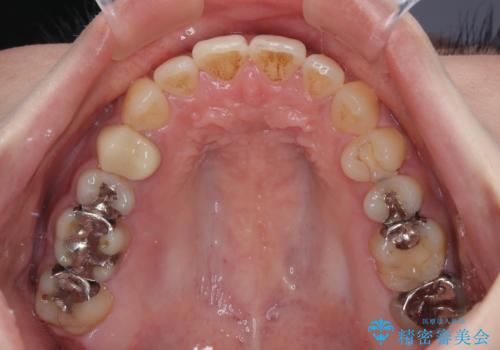

開咬をワイヤー装置で矯正治療

- 上下前歯が非接触となっている咬み合わせを気にして来院された患者様です。

開咬となっている原因の大半は、舌の突出癖によるものであるため、治療開始前から舌のトレーニングを開始し、スムーズに治療が進むようにしました。

開咬の方は、インビザライン矯正治療が適していますが、自己管理の煩わしさと、転勤の可能性がありマウスピース矯正であると通院しなくなるだろうとのことで、ワイヤー装置にて矯正治療を行うこととしました。